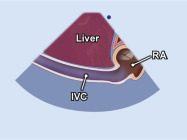

| 2.25. Mặt cắt dưới sườn cắt dọc tĩnh mạch chủ dưới (video 66) |

||||||||

|

|

Cửa sổ siêu âm dưới sườn

Ghi hình tĩnh mạch chủ dưới Cắt theo trục dọc của cơ thể người bệnh |

Tĩnh mạch chủ dước (IVC) cắt dọc | |||||